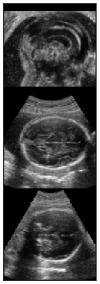

To quantitatively compare our network to the only other brain extraction method for fetal 3D US, the out test dataset was analysed with the method described in Namburete et al., 2018 [8]. The same experiments were performed and the results are shown in Table 3. Our network manages considerably better results throughout all comparisons. This is expected, since the other method relies on an approximation of the brain volume as ellipsoid, which does not accurately represent its shape. While an ellipsoid would be expected to have a high SC, its fitting to the probability mask results in an inaccurate alignment, which is reflected in the low SC of 0.74, compared to our network’s 0.95. This can be clearly seen in Fig. 7, where a comparison of their method with ours is shown.

| Original | Namb. 01 | Namb. 02 | Our work |